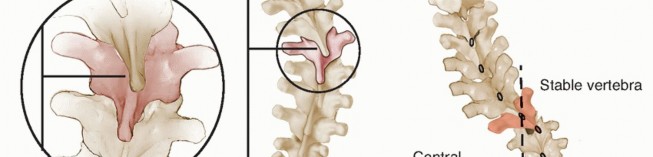

Standing posteroanterior (PA) radiographs on 36-inch cassettes characterize the spinal deformity by The magnitude of primary and compensatory curves, by the Cobb method (FIG 3)

FIG 3 • The Cobb method is used to measure the coronal deformity. Vertebral endplates (or the margins of pedicles) are used to extend lines as depicted for each of the curves involved. Lines orthogonal to these are then compared to determine the scoliosis angle. Vertebrae are typically selected to maximize the Cobb angle on each measurement.

FIG 3 • The Cobb method is used to measure the coronal deformity. Vertebral endplates (or the margins of pedicles) are used to extend lines as depicted for each of the curves involved. Lines orthogonal to these are then compared to determine the scoliosis angle. Vertebrae are typically selected to maximize the Cobb angle on each measurement.